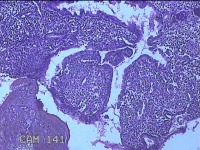

宫腔内容物

性别

女

年龄

36岁

临床诊断

右输卵管伞端妊娠流产?

一般病史

停经47天,阴道流血17天,下腹痛1天。

标本名称

大体所见

灰白暗红色不规则碎组织1.8x1.7x0.3cm一堆,未发现明显的绒毛样组织。

送检子宫内膜呈增生反应。